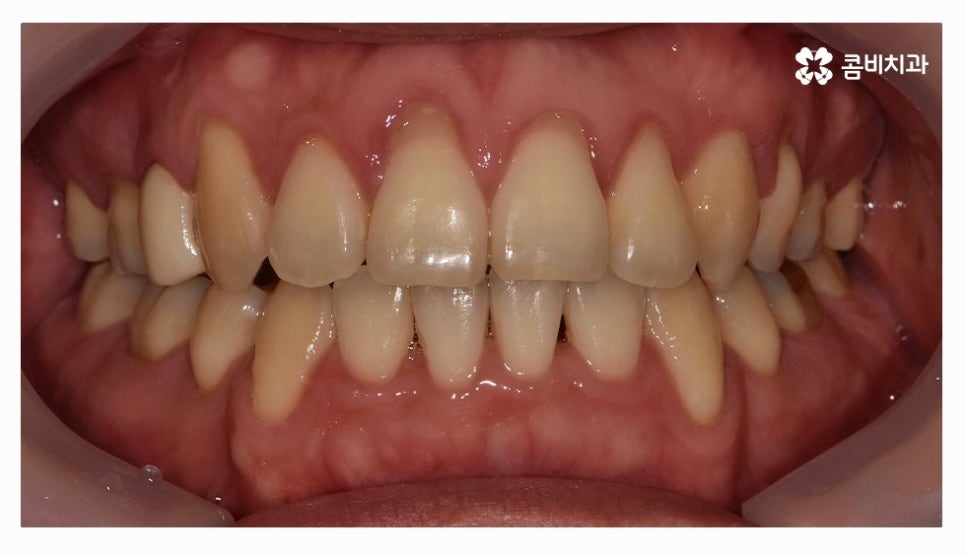

오늘 소개드릴 환자분은 윗니와 아랫니가 제대로 맞물리지 않는

부정교합 사례이며 클리피씨교정을 통해서 치료가 진행된 사례라고 할 수 있어요.

위 환자는 총 치료기간 약 30개월이 소요되었으며

개인에 따라 치료 기간 및 결과가 차이가 있을 수 있고,

개인에 따라 출혈 및 부작용이 발생할 수 있습니다.